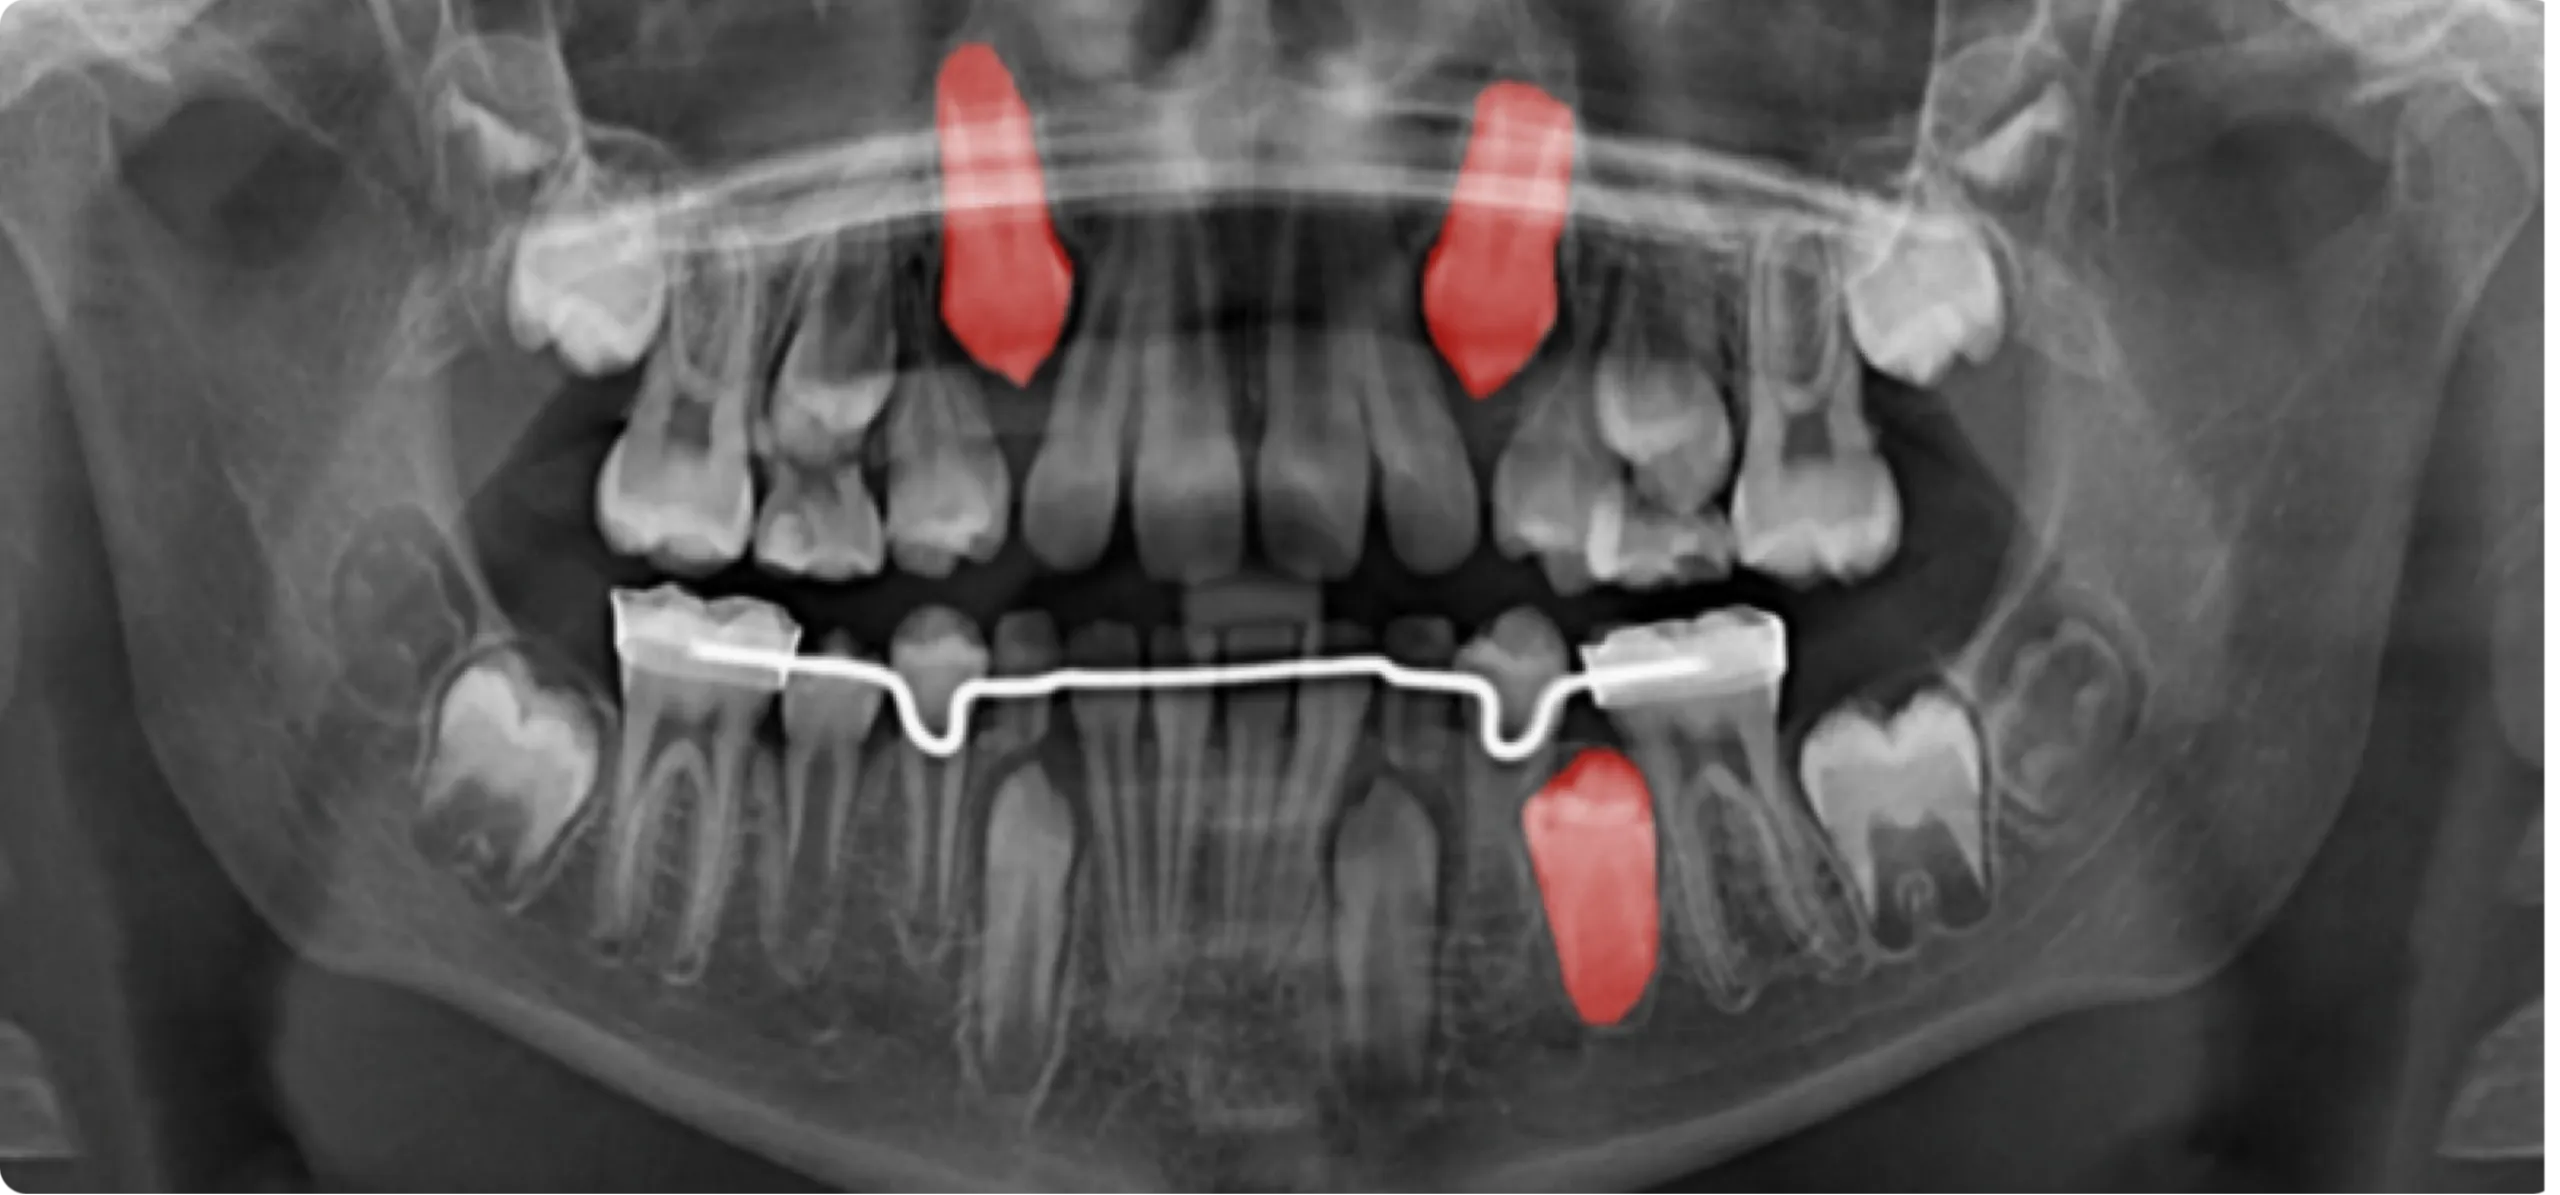

Sample of the first of twelve cases included in the online course Mixed Dentition Part 2